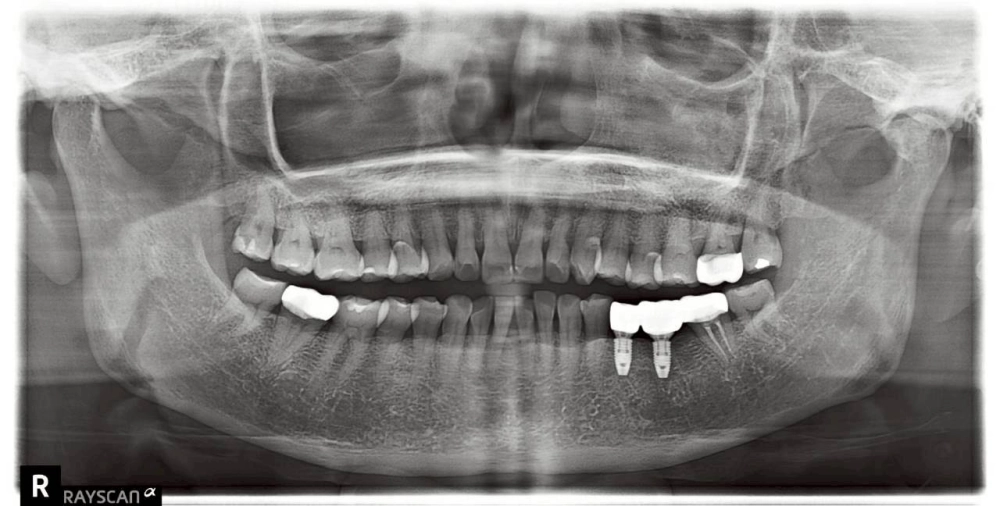

• 功能恢復(圖三): 裝上高度精準的假牙冠,完美銜接原有咬合曲線,恢復強勁咬合力。

術後回饋:找回對稱的咀嚼力

患者術後表示,終於能恢復雙邊均衡咀嚼的習慣,不僅進食速度變快,原本單側緊繃的感受也大幅緩解。